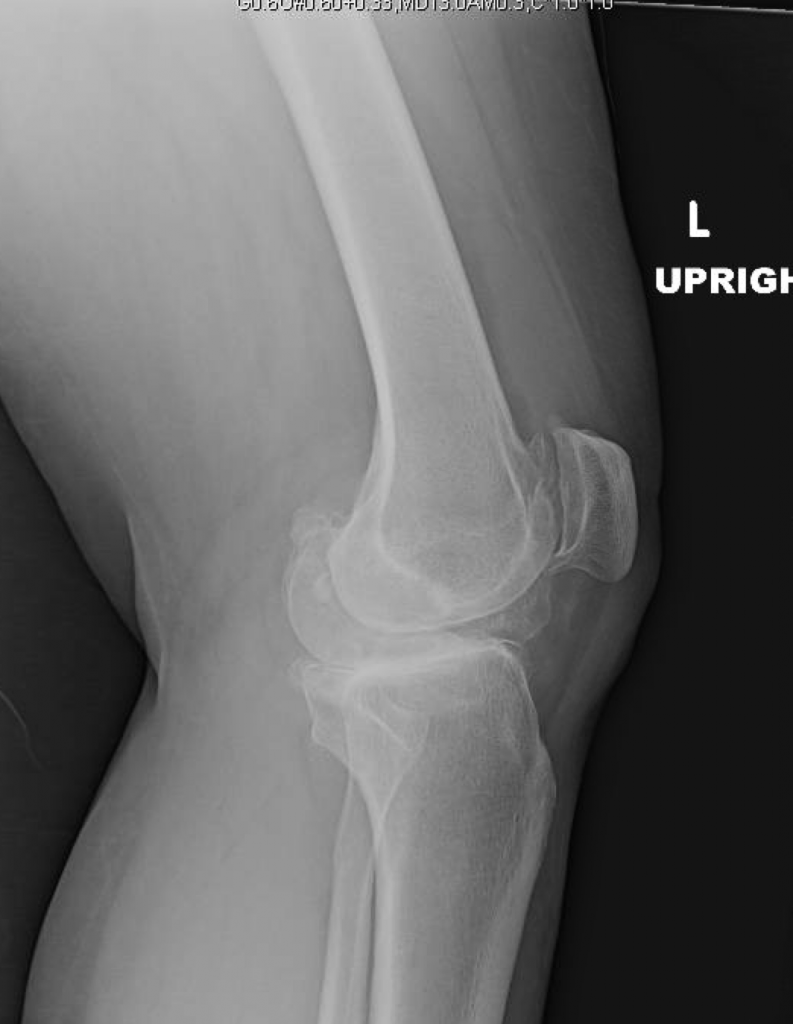

This is a 56 year old female with severe post-trauamtic arthritis of the left knee. She underwent prior knee arthroscopy, which failed. She had continuous pain, a significant limp, and a flexion contracture of 15 degrees.

The patient’s customized surgical plan and individualized implants were created specifically for her based off of a CT scan of her knee.